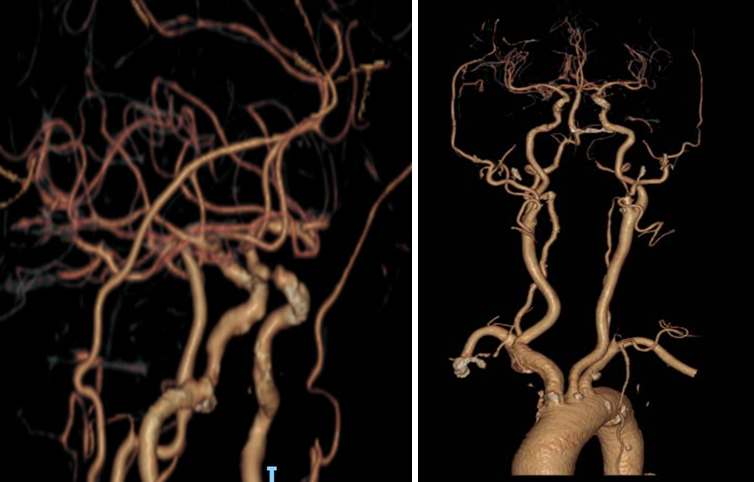

导丝怎么扩【载药时代 球扩天下】NOVA DES®颅内药物洗脱支架在颈内动脉颅内段重度狭窄中的应用体会二例!_https://www.jmylbn.com_新闻资讯_第20张

导丝怎么扩【载药时代 球扩天下】NOVA DES®颅内药物洗脱支架在颈内动脉颅内段重度狭窄中的应用体会二例!_https://www.jmylbn.com_新闻资讯_第21张

重要影像结论:右侧颈内动脉C4段重度狭窄;右侧颈内动脉C6段中度狭窄;左侧颈内动脉C5段中度狭窄;左侧大脑前动脉A1段重度狭窄。